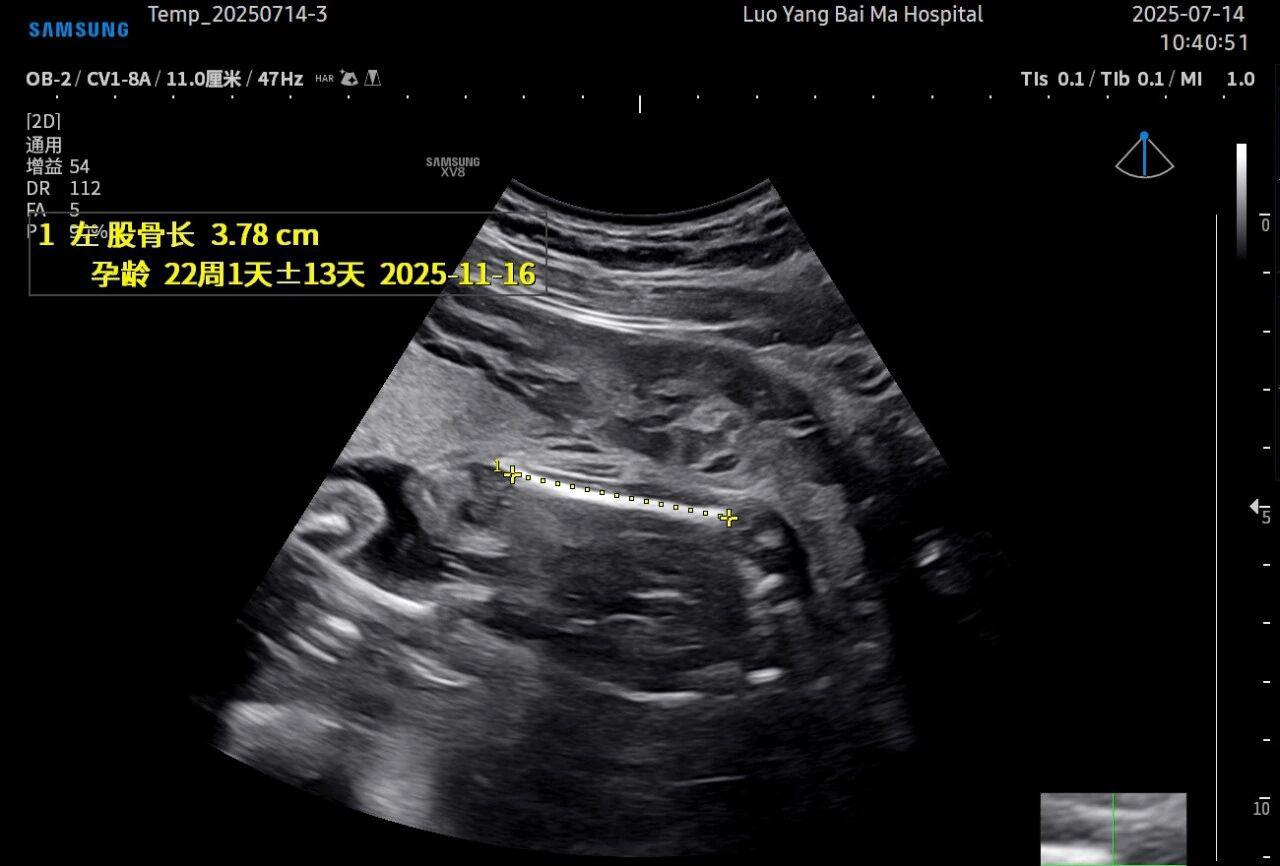

3. AI智能辅助,提升诊断效率与客观性

这是5D技术的核心优势之一。系统内置了强大的智能化大数据分析功能和AI辅助诊断工具。例如,在进行胎儿颈项透明层(NT)测量、胎儿长骨(LB)测量等关键生物学指标评估时,5D智能系统可以自动识别解剖层面、智能勾勒测量范围并进行计算。这不仅大大缩短了检查时间,更重要的是,它通过标准化的智能算法减少了因人为操作可能产生的误差,使诊断结果更加客观、可靠。

• 5D彩超检查通常建议在孕20-26周,尤其推荐在孕22-24周进行。此时胎儿大小适中,羊水量充足,图像清晰度较高。